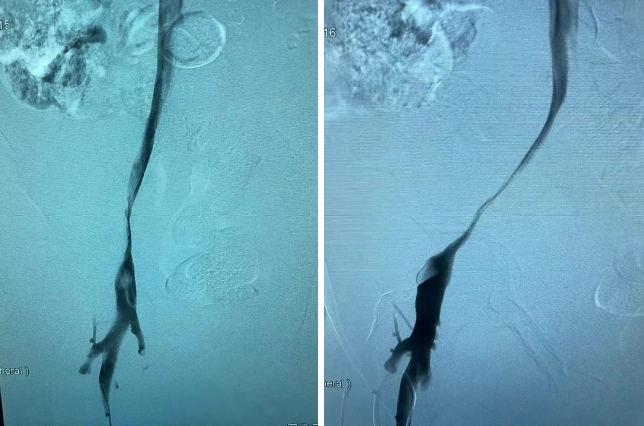

造影中证实患者右侧髂静脉重度狭窄。

右侧脐静脉重度狭窄

经与患者及其家属沟通后给予球囊扩张 支架植入术。术后继续抗凝治疗,患者下肢肿胀情况完全消失,血流通畅,患者感觉良好。

球囊扩张 支架植入术